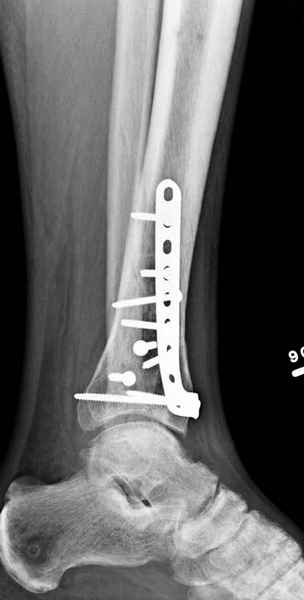

В приложении метафизарный перелом у ребёнка 14лет, с распространением линии перелома на зону роста.

В примере показан не перелом пилона, а эпифизеолиз, м/берцовую кость сознательно не фиксировал(длина её восстановлена, ротации нет),у детей стараемся минимизировать операц.травму, несколько позже разрешил полную нагрузку на ногу(4 недели). Но принцип фиксации б/берцовой кости м.б. таким же.

3. стабилизировать наружный опорный комплекс голени и предотвратить вальгусную деформацию голеностопного сустава. Конечно, данная проблема не очень актуальна, или вовсе не актуальна для 43С1, но для повреждений типа 43С2,3, особенно в случаях, когда метафизарный дефект потребовал пластики, а пластину пришлось уложить по медиальной стороне - остеосинтез малоберцовой кости является крайне необходимым - привожу характерный пример.

Но перелом малоберцовой кости может быть и много проксимальнее, и его так же приходится фиксировать из этих же соображений. И особенно, если пациент полный. Из отечественных хирургов на возможность развития такого осложнения - вальгусной деформации голеностопного сустава ч/з 2-3 месяца после операции при переломах типа 43С2 в отсутствии фиксации малоберцовой кости одним из первых указал Виталий Дрягин из ГКБ №3 Челябинска ещё в конце 90х.